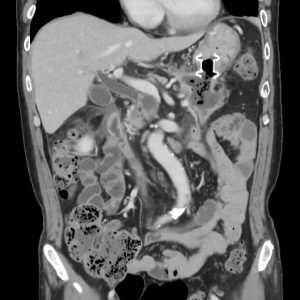

重症急性膵炎後のWONに対するEUS下膿瘍ドレナージ

肝門部胆管癌に対するEUS下胆道ドレナージ

急性胆嚢炎に対するEUS下胆嚢ドレナージ(LAMS留置)